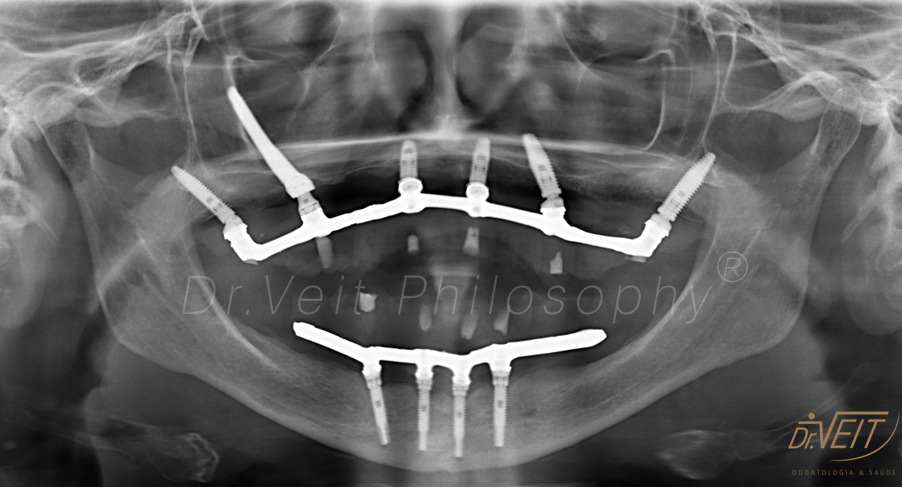

Arte de reabilitar os casos “impossíveis”. Pacientes que buscam a reabilitação oral podem conquistar um belo sorriso com segurança, mais conforto e tranquilidade com o uso do Implante Zigomático. A técnica possui o diferencial de realizar a implantação no osso zigomático e é indicada para casos de perda óssea maxilar avançada.